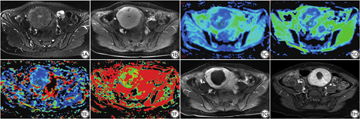

记录肌瘤类型(黏膜下、肌壁间、浆膜下),肌瘤位置(前壁、侧壁、后壁、底壁)。在T2WI矢状位图像上测量腹壁厚度、肌瘤腹皮距(肌瘤腹面到腹壁皮肤的最小距离)、肌瘤背骶距(肌瘤背面到骶骨的最小距离)。肌瘤的体积通过测量横径(a)、左右径(b)、上下径(c)三个径线获得。体积计算公式为:V1=0.5233×a×b×c。根据肌瘤在T2WI序列上信号强度与骨骼肌对比,将其T2WI信号分为均匀低信号、均匀等信号、均匀高信号、混杂高低信号四种类型。根据肌瘤与子宫肌层强化程度的对比,将其强化方式分为轻度强化、中度强化、显著强化三种强化类型。

所有数据后处理在ADW 4.4图形工作站上利用Func tools软件进行,在肌瘤最大层面上勾画感兴趣区域(region of interest, ROI),测量时避开钙化、坏死、血管及出血区域,取得以下参数:标准表观扩散系数(standard apparent diffusion coefficient, StandardADC)值、快速表观扩散系数(FastADC)值、慢速表观扩散系数(SlowADC)值、灌注分数(f)值。所有参数测量三次取平均值。以上各数据测量及图像判定由两位影像科医师(1位23年腹部影像诊断经验的副主任医师、1位10年腹部影像诊断经验的主治医师)分别采用双盲法进行。

对可能影响子宫肌瘤患者HIFU术后再干预的14个变量(年龄、腹壁厚度、肌瘤腹皮距、肌瘤背骶距、肌瘤最大径、肌瘤体积、肌瘤位置、肌瘤类型、T2WI信号类型、T1WI强化类型、StandardADC值、SlowADC值、FastADC值、f值)进行单因素Kaplan-Meier法分析及Log-Rank检验,其中的定量资料用X-tile软件计算其最佳截断值将其分为两组。依据既往报道[21],根据肌瘤消融难易程度,肌瘤位置分为前壁、底壁、侧壁、后壁4组,肌瘤类型按黏膜下型、浆膜下型、肌壁间型分为3组。结果显示,年龄、T1强化类型、T2信号类型、肌瘤体积、SlowADC值、StandardADC值共6个因素影响子宫肌瘤HIFU术后再干预(P<0.05),而肌瘤位置、肌瘤类型、肌瘤最大径、FastADC值、f值、腹壁厚度、肌瘤腹皮距、肌瘤背骶距与子宫肌瘤HIFU术后再干预无关(表1、图1)。